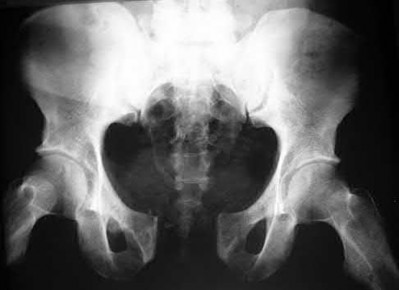

During head-on motor vehicle collisions occurring at highway speeds, airbag-protected individuals have a decreased rate (as compared to non-airbag protected individuals) of all of the following EXCEPT:

Corrent answer: 4

The referenced study by Loo et al. studied the interaction between airbags/seatbelts and mechanism of the crash (ie. front vs. side impact) and the injury patterns in these patients. They found that in frontal crashes, airbags reduced Glasgow Coma Scale severity in brain injury, facial fracture, shock, thoracoabdominal injuries and the need for extrication. Frontal airbags also had a protective effect on lower extremity fractures, but had no significant protective effect on pelvic fractures.